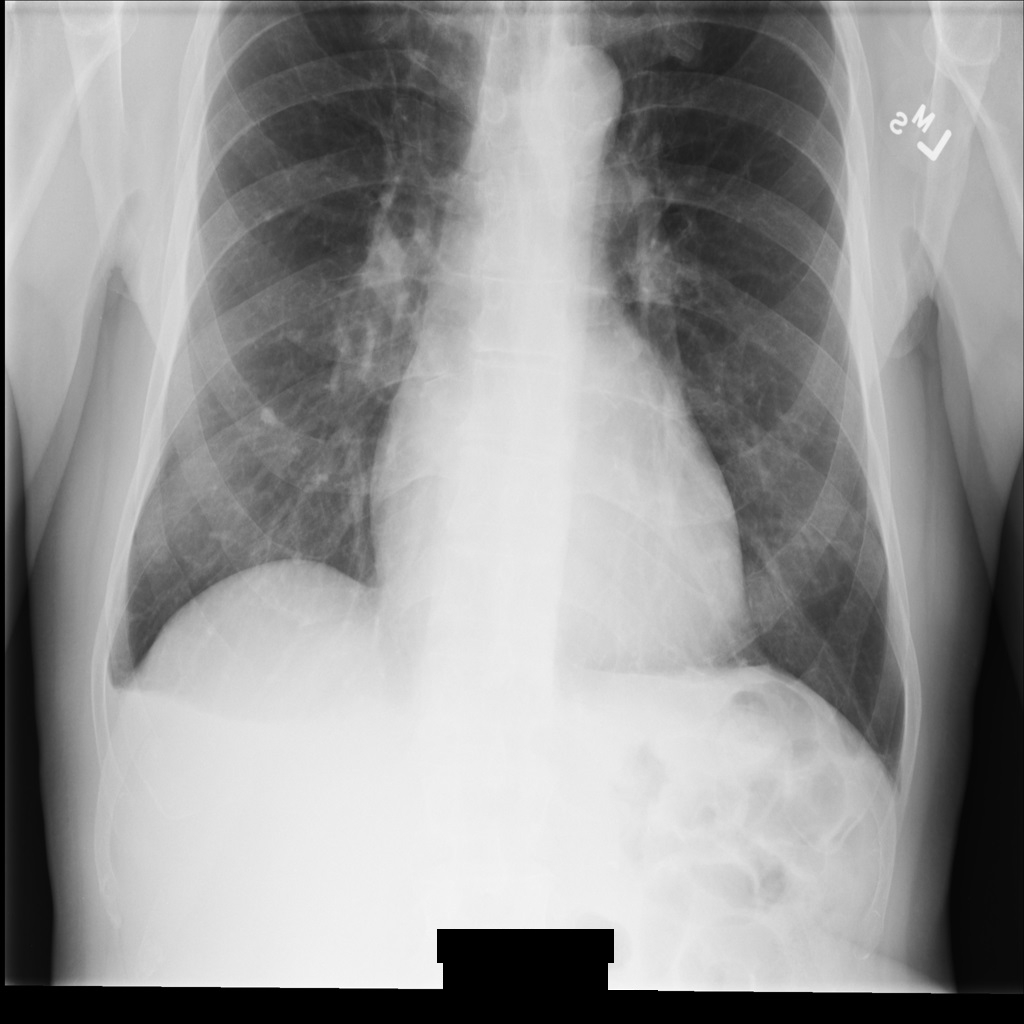

Después de anonimizar la imagen con REDACT_ALL_TEXT, la imagen tiene este aspecto. Fíjate en que se ha ocultado todo el texto superpuesto en la parte inferior de la imagen.

REDACT_ALL_TEXT.Ocultar texto sensible con la opción Limpiar descriptores

Después de anonimizar la imagen con REDACT_SENSITIVE_TEXT_CLEAN_DESCRIPTORS, la imagen tiene este aspecto. Ten en cuenta que no se ha ocultado todo el texto superpuesto en la parte inferior de la imagen. El texto Female sigue mostrándose porque PatientSex (0010,0040) no es uno de los infoTipos DICOM predeterminados.

REDACT_SENSITIVE_TEXT_CLEAN_DESCRIPTORS.Desidentificar etiquetas DICOM